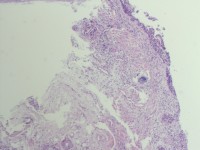

咔血3月,纤维支气管镜:右侧肺下叶基底段黏膜增生。能诊断肺部鳞状细胞癌吗?

鳞癌。